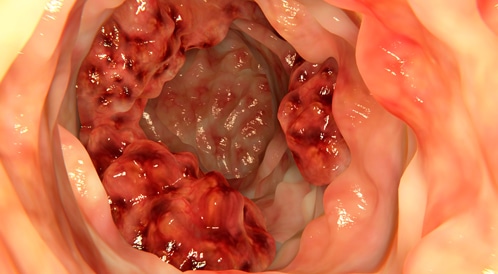

من أين يأتي سرطان المستقيم؟

يحدث سرطان المستقيم نتيجة لحدوث تغييرات غير طبيعية في الحمض النووي (DNA) لخلايا المستقيم، وهو الجزء الأخير من الأمعاء الغليظة، فتؤدي هذه التغيرات الجينية إلى خلل في آلية عمل الخلية؛ إذ تبدأ الخلية في النمو والانقسام بشكل غير منتظم وسريع، دون أن تمر بمرحلة الموت الطبيعي كما هو مفترض في الخلايا السليمة.

وبمرور الوقت، تتراكم هذه الخلايا لتكوّن ورمًا سرطانيًا قد يغزو الأنسجة المجاورة ويدمرها، بل ويملك القدرة على الانتقال إلى أعضاء أخرى من الجسم فيما يسمى "السرطان النقيلي".